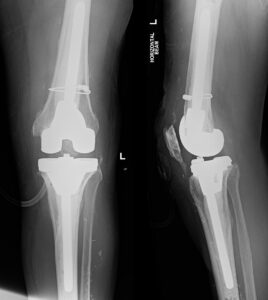

Knee Procedures Total Knee Replacement A knee replacement is a surgical procedure in which damaged or worn-out parts of the knee joint are removed and replaced with artificial components. It is typically done to reduce pain and improve function in people with severe knee joint damage, often caused by arthritis or injury. Partial Knee Replacement A knee replacement is a surgical procedure in which damaged or worn-out parts of the knee joint are removed and replaced with artificial components. It is typically done to reduce pain and improve function in people with severe knee joint damage, often caused by arthritis or injury. Revision Knee Replacement Revision knee replacement is a surgical procedure to replace or repair a previous knee prosthesis that has become loose, worn out, or infected. It involves removing the old implant and installing a new one to restore knee function and relieve pain. High Tibial Osteotomy High tibial osteotomy is a surgery that involves cutting and reshaping the upper part of the shinbone (tibia) to realign the knee joint. It is often performed to relieve arthritis pain in young, active patients by shifting weight away from damaged cartilage. ACL Reconstruction ACL reconstruction is a surgical procedure to replace a torn anterior cruciate ligament (ACL) in the knee with a graft, usually taken from the patient's own tissue or a donor. It aims to restore stability and allow return to normal activity levels following ligament injury. Meniscal Surgery Meniscal surgery involves repairing or removing damaged meniscal cartilage in the knee, which cushions and stabilizes the joint. The procedure can help relieve pain, restore knee function, and prevent further joint degeneration. Patellofemoral Stabilisation Patellofemoral stabilisation is a procedure to realign or secure the kneecap (patella) when it tends to dislocate or drift out of place. It aims to improve knee stability and prevent recurrent dislocations or pain.